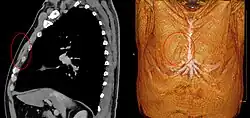

The presence of the sternalis in sagittal plane on CT (left) and on volume rendered CT 3D reconstruction (right).

The presence of the sternalis is asymptomatic[1] but aesthetic complaints have been reported as it was reported to cause chest asymmetry or deviation of the nipple-areola complex.[1][15] The presence of the sternalis may cause alterations in the electrocardiogram[16] or confusion in mammography.[17] However, there is a potential benefit of the muscle as it can be used as a flap in a reconstructive surgery of the head and neck and the anterior chest wall.[15]